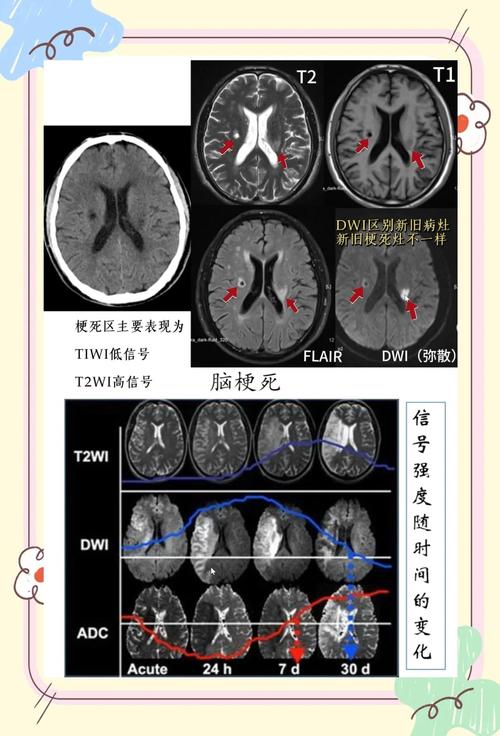

| CT影像表现 | 发病早期(6小时内)可能正常,6小时后逐渐出现低密度灶,边界不清,可伴有占位效应(脑组织水肿,导致中线移位)。 | 急性期可能看不到或仅表现为一个微小的、边界清晰的低密度灶。 慢性期表现为一个边界清晰、圆形或卵圆形的小低密度灶,无占位效应。 |

(图片来源网络,侵删)- 对于超早期的脑梗(<6小时),CT可能完全正常,此时需要更敏感的MRI(磁共振),特别是DWI序列来发现病灶。

- 对于非常新鲜的、极小的腔梗,CT可能也看不清,MRI对微小病灶的显示能力远优于CT。